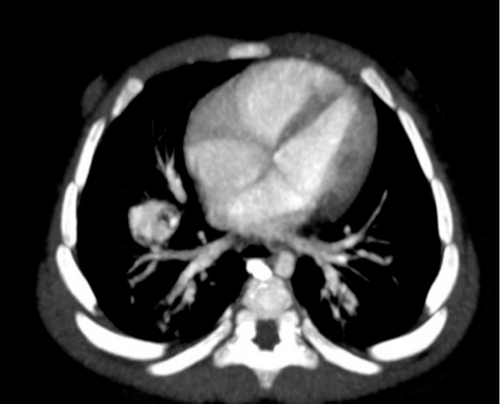

Al año de finalizar el tratamiento con propanolol se realizó nuevo TC torácico, en el que se aprecian, en la zona donde la paciente presentaba la malformación vascular, pequeñas imágenes de paredes finas que en su conjunto miden 8 x 10 mm, de aspecto residual (Fig. 4).

Figura 4. Principales imágenes radiológicas del caso: TC pulmonar de control